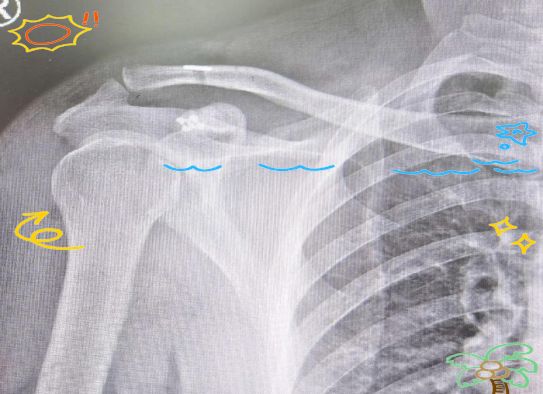

近日,我院骨傷科迎來了一位因右肩鎖關節(jié)脫位而前來就診的青年患者黃先生。他是在騎自行車時不慎跌倒,導致右肩部受傷。經過詳細檢查,我們發(fā)現黃先生右肩鎖關節(jié)處存在一個明顯的凹陷,同時關節(jié)松動,按壓時具有浮動感,這進一步確認了右肩鎖關節(jié)脫位的診斷。

接下來,我們將為黃先生進行微創(chuàng)手術,以解決這一困擾他的問題。由于黃先生的肩鎖關節(jié)全脫位,屬于Ⅲ型損傷,其關節(jié)囊、肩鎖韌帶及喙鎖韌帶均已斷裂,導致肩鎖關節(jié)完全喪失穩(wěn)定性,因此必須通過手術進行修復。若采用傳統的克氏針張力帶及鎖骨鉤板固定方式,不僅需要二次手術取出,而且鎖骨鉤板手術還可能引發(fā)肩峰撞擊綜合征,增加治療費用及創(chuàng)傷。經過深入討論和溝通,骨傷科團隊決定采用帶袢鋼板技術來治療黃先生的右肩鎖關節(jié)脫位。在幫扶專家潘宇朝主任醫(yī)師的帶領下,骨科團隊成功為黃先生實施了微創(chuàng)帶袢鈦板系統內固定術。

黃先生因騎自行車跌倒導致右肩鎖關節(jié)脫位,經診斷為Ⅲ型損傷。由于其關節(jié)結構嚴重損傷,需要手術修復斷裂的結構。鑒于傳統方法需二次手術且創(chuàng)傷較大的缺點,我們選擇采用微創(chuàng)帶袢鋼板技術進行治療。

術后,黃先生的肩鎖關節(jié)已成功復位,且微創(chuàng)切口僅有幾厘米大小。相較于傳統的鋼板內固定術,微創(chuàng)帶袢鈦板系統內固定術的復位效果更為精準,創(chuàng)傷程度顯著降低,更值得一提的是,它甚至可以免除二次手術的痛苦。帶袢鋼板,亦被稱作帶袢鋼板或Endobutton,其獨特之處在于通過在鎖骨遠端與喙突間構建一個新的韌帶固定點,從而模仿原有的喙鎖韌帶功能,進而實現肩鎖關節(jié)穩(wěn)定性的重建。相較于傳統的治療方法,帶袢鋼板治療法展現出創(chuàng)傷更小、恢復更快、疼痛感更低以及并發(fā)癥更少的顯著優(yōu)勢,并且通常無需進行二次手術即可取出內固定物。目前,帶袢鋼板已被公認為是肩鎖關節(jié)脫位治療領域的金標準。